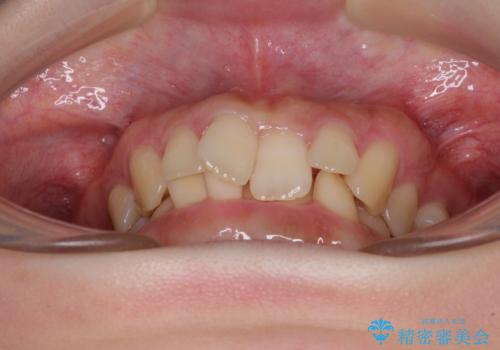

- 全体的な歯列の叢生を気にして来院された患者様です。

奥歯の咬み合わせを見ると、片方は上顎が下顎に対して相対的に前方にあり、他方は交叉した咬合の状態でした。

咬み合わせを改善するためには、上顎臼歯を後方に移動させた咬み合わせにする必要があります。

インビザライン単体で改善することも可能ですが、ディープバイトのためインビザライン単体で達成する可能性が低いと考えられたため、カリエール・ディスタライザーという補助装置を併用して、より確実性を上げることとしました。